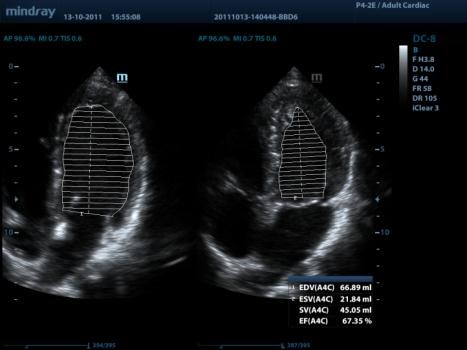

AutoEF

Интеллектуальный способ анализа изображений двухмерной эхокардиографии для автоматического распознавания диастолических и систолических кадров и вывода результатов КДО, КСО, реакции выброса и т. д. методом Симпсона

Auto LV (автоматическое измерение левого желудочка)

Простая процедура измерения левого желудочка с функциями автотрассировки и простой ручной коррекции.